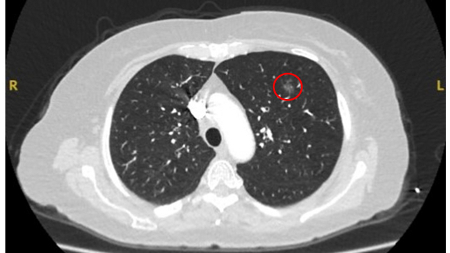

Nódulos com opacidade em vidro fosco: um crescimento de 2 mm no diâmetro máximo deve ser considerado potencialmente significativo, enquanto o desenvolvimento de um componente sólido sugere a necessidade de considerar uma investigação e/ou tratamento adicionais.[Figure caption and citation for the preceding image starts]: Tomografia computadorizada (TC) mostrando nódulo com opacidade em vidro fosco no lobo superior esquerdo. Este foi eventualmente ressecado após 2 anos de vigilância em decorrência de crescimento, e a histopatologia confirmou adenocarcinoma de pulmão com padrão mucinoso-lepídico mistoDo acervo de Dr. George Tsaknis, MD, PhD, FRCP (Londres), MRQA, MAcadMEd, PGCert; usado com permissão [Citation ends].